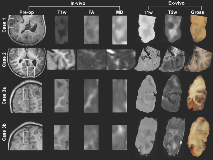

Rationale: To clarify the basis of abnormal diffusion in Tuberous Sclerosis Complex (TSC) in the proximity of epileptogenic tubers, we correlated ex vivo high-resolution diffusion imaging of white matter, perituber and tuber regions with histopathology. Methods: Three 'en-block' epilepsy surgical specimens from children with TSC were scanned in a 3T or 7T MRI with a structural image isotropic resolution of 137-300 micron, and diffusion image isotropic resolution of 270-1,000 micron. Next, we stained four specimens for myelin (luxol fast blue, LFB) and gliosis (glial fibrillary acidic protein, GFAP), and registered digitized slides (0.686 micron resolution) to high-resolution ex vivo MRI for histopathological comparison.Figure 1: Pre-operative imaging and orientation of resection specimens ex vivo.Resection regions are highlighted in the white rectangle in the preoperative images.  Magnified frames of T1-weighted (T1w), fractional anisotropy (FA) and mean diffusivity (MD) are shown, and compared to the ex vivo images on the right. Note that the imaging plane is manipulated to match the ex vivo cutting plane and histopathology slides; e.g. case 1 is a pseudo-axial plane, and images may be inverted along any axis.  Results: In white matter and perituber regions, LFB optical density (OD) correlated with fractional anisotropy (FA) and inversely with mean diffusivity (MD) and T2w intensity. In white matter but not perituber tissue, GFAP OD correlated with MD and T2w, and inversely with FA. In tubers and in the cortex, there  was little variation in mean LFB and GFAP signal intensity, and no correlation with MRI metrics.Figure 2: Example: Quantitative comparison of histopathology and ex vivo MRI for case 2(LEFT ) Luxol fast blue (LFB) stain, after color deconvolution. (RIGHT ) Glial fibrillary acidic protein (GFAP) stain, after color deconvolution.In the left column, ex vivo structural images (T1w, T2w) and diffusion imaging (fractional anisotropy FA, mean diffusivity MD). On the top row, the regions of interest (ROIs) are placed in specific ultrastructural tissue types: Cortex, tuber, perituber, and white matter. In the last column, two tissue types (perituber and white matter) are merged, yielding a wider variability. The colored dots indicate intensity histograms, and the hot colors indicate more overlap between MRI metrics and histopathology optical density values. Spearman’s Rho correlations are listed, and regression lines are shown for higher values. Conclusions: These findings suggest diffusion imaging abnormalities in microscopic tissue types correspond to specific histopathological markers in TSC. Funding: J. Peters, B. Scherrer, S. Prabhu, M. Sahin, and S. Warfield are supported by NIH R01 NS079788 and U01 NS082320 grants. A. Prohl is supported by Harvard Catalyst | The Harvard Clinical and Translational Science Center (National Center for Research Resources and the National Center for Advancing Translational Sciences, NIH award UL1 TR001102). S. Prabhu is also supported by the Department of Defense W81XWH-11-1-0365. M. Sahin is additionally supported by NIH U54 HD090255 and U54 HD090255 grants and the Boston Children’s Hospital Translational Research Program. The Developmental Synaptopathies Consortium (U54 NS092090) is part of the NCATS Rare Diseases Clinical Research Network (RDCRN). RDCRN is an initiative of the Office of Rare Diseases Research (ORDR), NCATS, funded through collaboration between NCATS, NIMH, NINDS, and NICHD. We thank the Harvard Medical School Neurobiology Department and the Neurobiology Imaging Facility for consultation and instrument availability that supported this work. This facility is supported in part by the Neural Imaging Center as part of an NINDS P30 Core Center grant #NS072030.